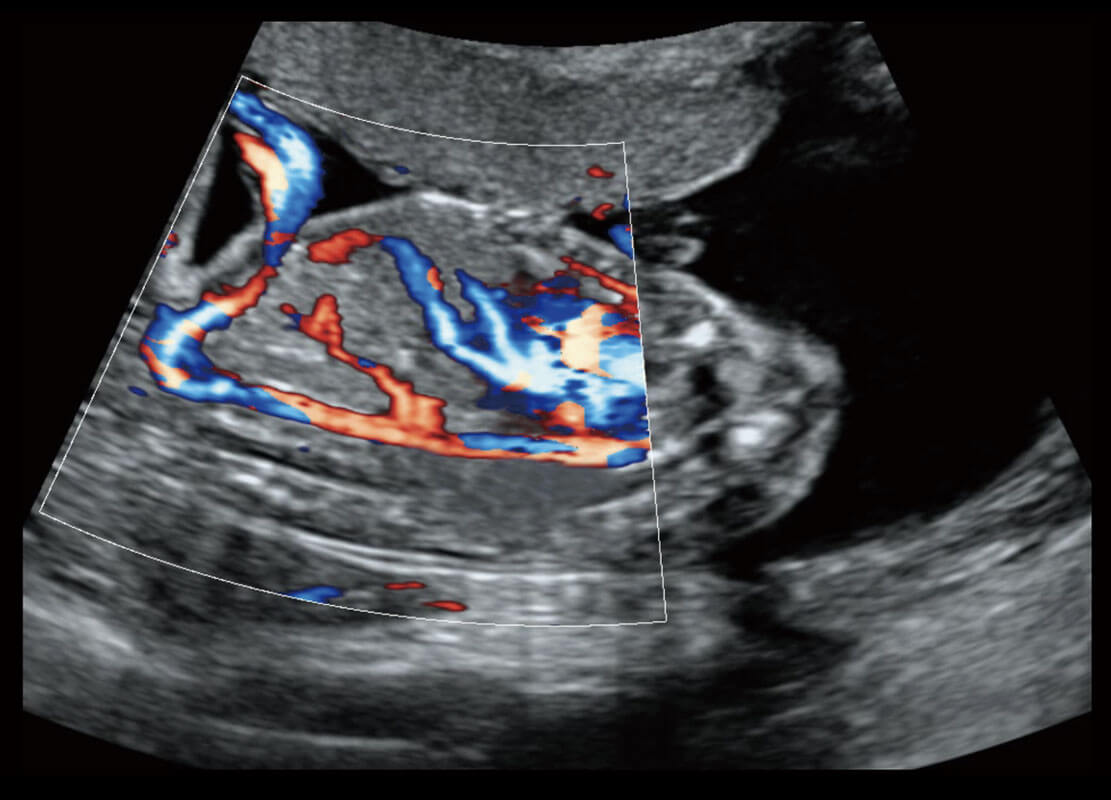

P60优异的图像质量搭载专科探头,在妇科基础疾病的诊断、卵泡生长的监测、输卵管通畅情况的判别等方面为您提供生殖应用方案。

腔内妇科-宫腔分离

腔内妇科-卵巢